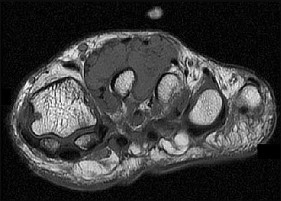

Surgical repair of the injury shown in the MRI scans in Figures 1 through 4 through a single-incision approach has a higher incidence of

The MRI scans show a distal biceps tendon avulsion with significant retraction. When addressing these injuries, a single-incision approach has been associated with an increased risk of lateral antebrachial cutaneous nerve injury. A two-incision approach has been associated with an increased risk of heterotopic ossification, second surgeries and posterior interosseous nerve injury.